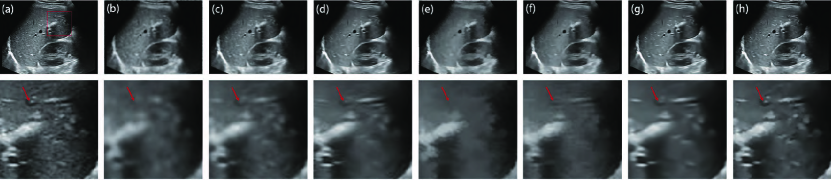

The parameter is the iteration number. We integrate into the diffusion coefficient, as shown in (16). If is set to a large number, a small diffusion coefficient will be obtained. This strategy will overcome the problem inherent in the traditional AD model that tends to decrease the edge feature contrast as increases. Fig. 5 depicts the despeckled results of different . In the case of , our filter has removed the speckle noise while preserving features properly. As the increases, features are all effectively protected to the same extent. To reduce the required time for despeckling, we set .